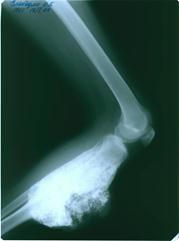

Остеосаркома

Рис.3.Остеосаркома лучевой Рис.4.Остеосаркома большеберцовой кости.

кости.

Характерно поражение метафизов длинных трубчатых костей (см.рис.3 и 4).. Наиболее частая локализация (примерно 50% случаев) - область коленного сустава- дистальная часть бедра и проксимальная часть большеберцовой кости. Часто также поражается проксимальная часть плечевой кости и бедренной кости, и средняя треть бедренной кости. Поражение плоских костей, особенно таза в детском возрасте встречается менее чем в 10% случаев .